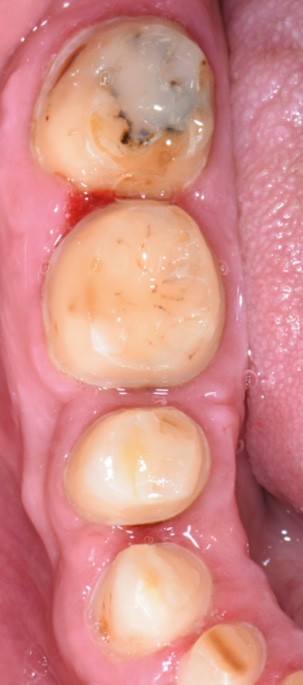

Au vu du contexte para-fonctionnel et de l’étendue de la perte tissulaire, des coiffes périphériques minimalement invasives ont été choisies afin de restaurer l’esthétique et la fonction. Actuellement, aucun consensus n’est fait sur le choix du matériau d’infrastructure à privilégier. Les matériaux hybrides usinables présentent des propriétés mécaniques, physiques et biologiques intéressantes en contexte d’usure sévère (e.g., module d’élasticité, résistance à la propagation de fêlures, facilité de réintervention). Une réhabilitation globale avec remontée de dimension verticale d’occlusion (DVO) par l’intermédiaire de coiffes composites renforcés en nano-céramiques est décrite.